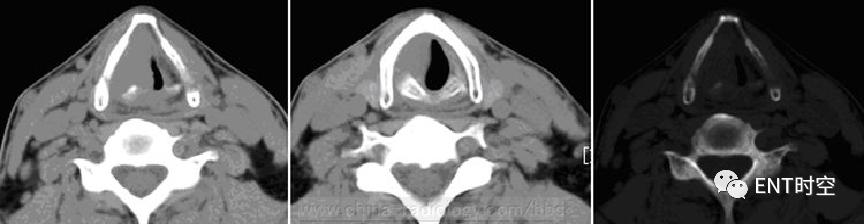

误咽金属异物后咽痛、吞咽困难7天。

左侧颈动脉鞘前区及左侧杓横肌区可见一条状高密度异物影,异物周围可见软组织肿胀,呈稍低密度,边界不清。左侧梨状隐窝闭塞并可见软组织突入喉前庭,食管走行区可见管状高密度胃管影

左侧喉咽部及杓横肌左侧异物伴感染(有明确病史并经手术确诊)